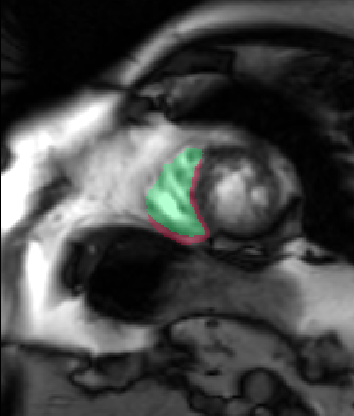

Table 2 summarizes the results of our method for RV segmentation in terms of image-based metrics. The results show that the algorithm performs better at ED than ES. This can be explained by the fact that the image quality is higher at ED than at ES. By analyzing the DM and HD on a slice-basis, it can be seen that the proposed method has a high performance on basal slices, with an average and . However, the segmentations on apical slices are of lower quality affecting the overall DM and HD scores. Figure 3 shows segmentation results in six different cases obtained from the challenge that illustrate the differences between basal and apical segmentations.

The results show that the method perform well on average but there are some cases in which it fails. In particular, our method has a very high performance on the basal slices, whereas the scores obtained for apical slices are lower (Figure 3). These can be explained by two factors: 1) The image quality at the apical slices is rather low. As the registration, the atlas ranking and the label fusion are intensity-based, poor image quality can affect the results, and 2) the regions to be segmented at the apical slices are rather small, which implies that the atlases’ masks are also small at these slices. When the masks are used in the registration process to supress undesired structures, the remaining information is insufficient, causing the intensity-based registration, rigid or non-rigid, to fail.

In conclusion, we have presented a fully automatic segmentation method applied to the extraction of RV epicardium and endocardium. The results show that the method is in average succesful in the segmentation results. The segmentations obtained in the basal slices are of very high quality, whereas the results in the apical ones are less good mainly because the registration stage fails to properly align the atlases with the unseen image.